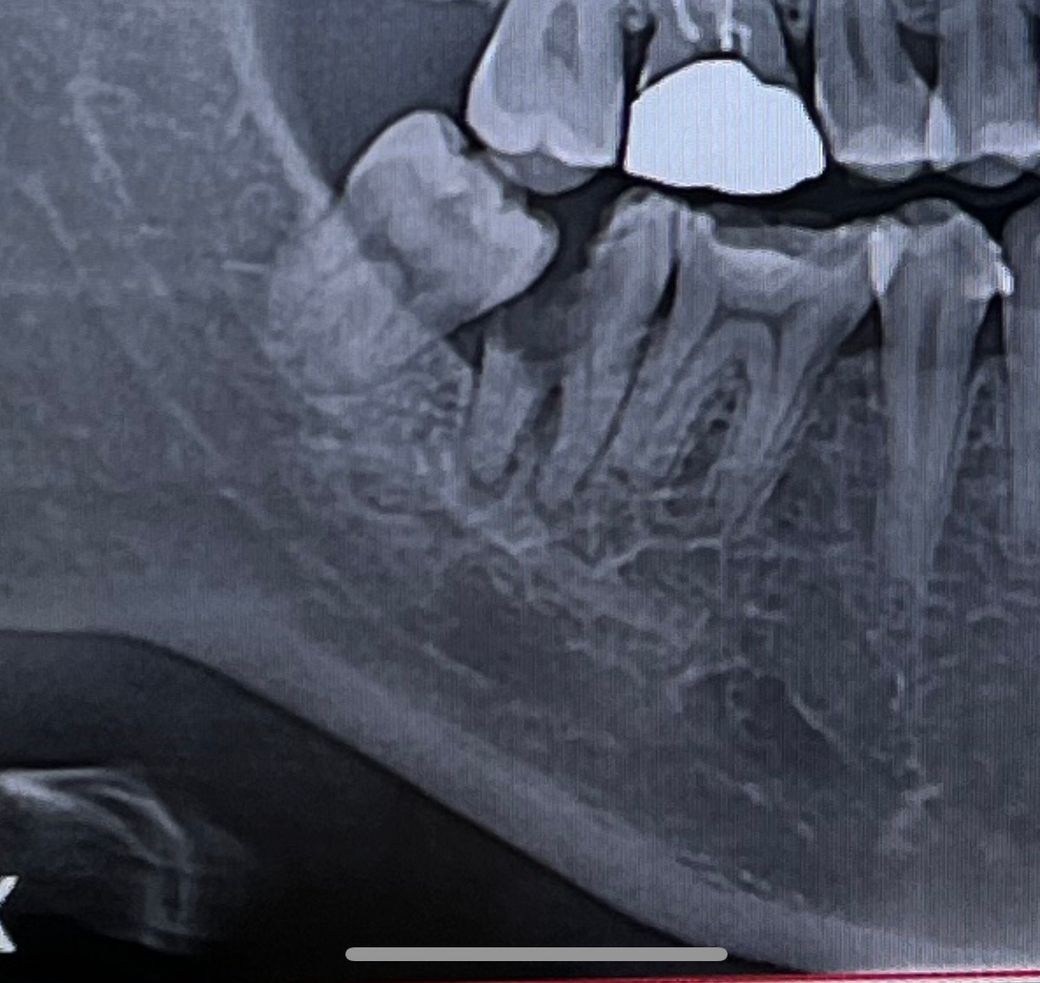

이가 썩어도 너무 썩었습니다 무조건적인 발치는 피하고 싶어요.. 뿌리를 살리지 못하는 경우인가요??

아래 어금니입니다 ㅠㅠㅠ

현재 뿌리까지 손상이 온것으로 보이기에 이 경우에는 발치후에 임플란트 치료가 필요로 됩니다.

충치가 잇몸뼈 아래까지 위치하고 있으면 해당 부위가 건조되지 않기 때문에 치과 재료로 충전을 하기 힘들 수 있습니다. 사진으로 봤을 경우 뿌리 쪽으로 깊게 내려가 있는 충치가 예상됩니다.

사랑니를 발치한 후 해당 부위가 건조시킬 수 있다면 치료를 할 수 있을 것으로 생각되나 그러지 못한다면 발치를 해야 할 수 있습니다. 자세한 확인을 위해서 치과에서 진료를 받아 받아보세요.

사진상으로 보면 충치가 너무 심하게 진행되서 발치를 하셔야될것같습니다. 뿌리를 남겨 놓는건 큰 의미가 없습니다.

웬만하면 치아를 살리고 싶겠지만 해당 사진으로 봐서는 대부분의 치과에서 임플란트를 권할겁니다.

사랑니 옆 두번째 어금니는 충치가 너무 심해서 발치가 불가피할 것 같습니다 한가지 방법은 어금니, 사랑니를 빼고 사랑니를 옆으로 심어 이식하는 것입니다